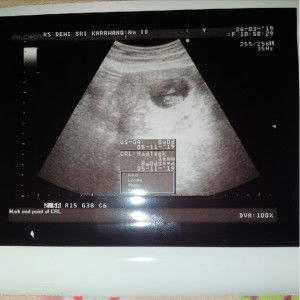

bunda2 dsni usia kehamilan brp w nafsu mkn kembali normal, soal nya aku sekrg hamil 11 w tpi blm nafsu mkn ??